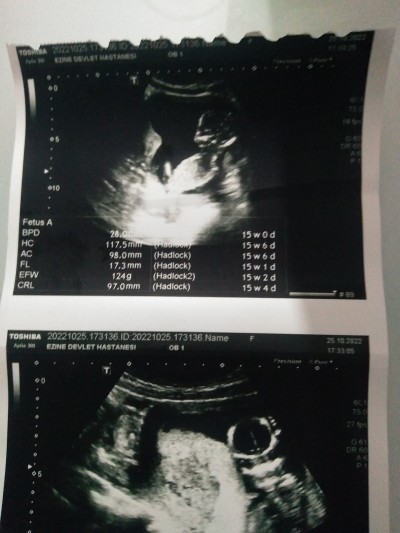

Ultrason kağıdı varsa resmini at

Bnmkisi 14 haftalık ta 97 mm di

bu bnmki ve bi türlü netleşme di